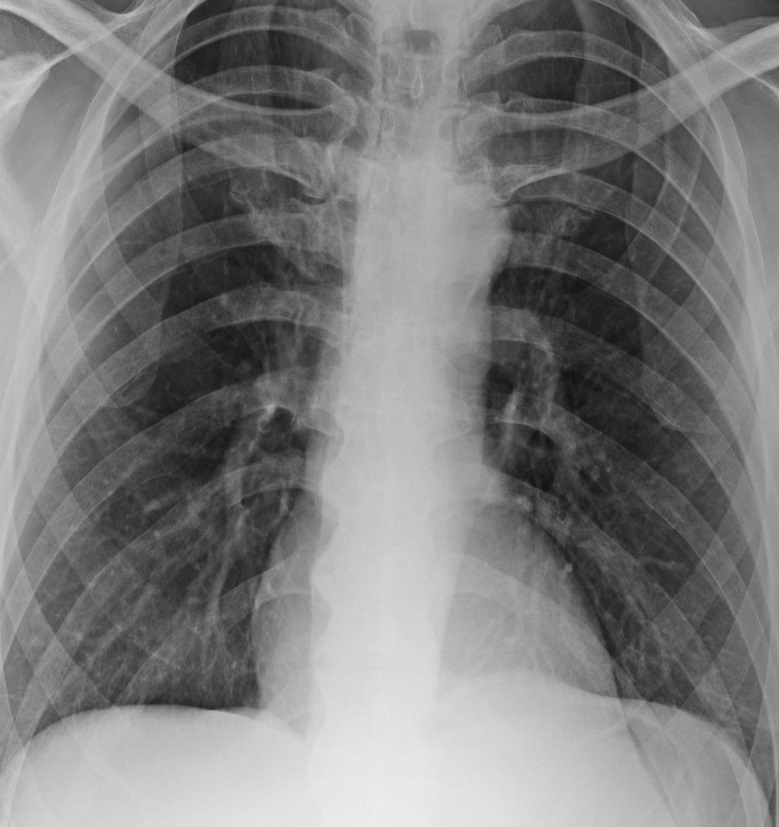

Figure 6 presents image examples for each class retrieved from the RYDLS-20 database. It is worth to mentioning that we have no further information concerning the CXR images with regarding the CXR machine used to take the image, as well as the origin, age and ethnicity of the people whose these images belong to.

Refer to caption

(a) Normal.

(b) COVID-19.

(c) SARS.

(d) MERS.

(e) Pneumocystis.

(f) Streptococcus.

(g) Varicella.

Figure 6: RYDLS-20 image samples.